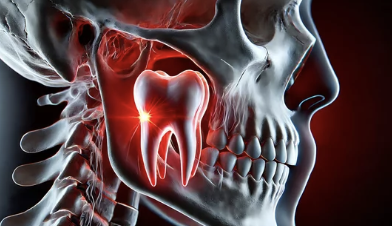

사랑니가 잇몸 아래에서 정상적으로 자라지 못하고, 잇몸 안이나 다른 치아에 눌려 비정상적인 방향으로 자라는 상태를 매복 사랑니라고 합니다. 매복의 정도는 다음과 같이 나뉩니다:

- 부분 매복: 사랑니 일부가 잇몸 밖으로 나와 있는 상태.

- 완전 매복: 사랑니가 완전히 잇몸 아래에 매복된 상태.

- 턱뼈의 크기가 작아서 사랑니가 자랄 공간이 부족함.

- 치아의 발육 방향이 잘못되어 주변 치아를 압박.